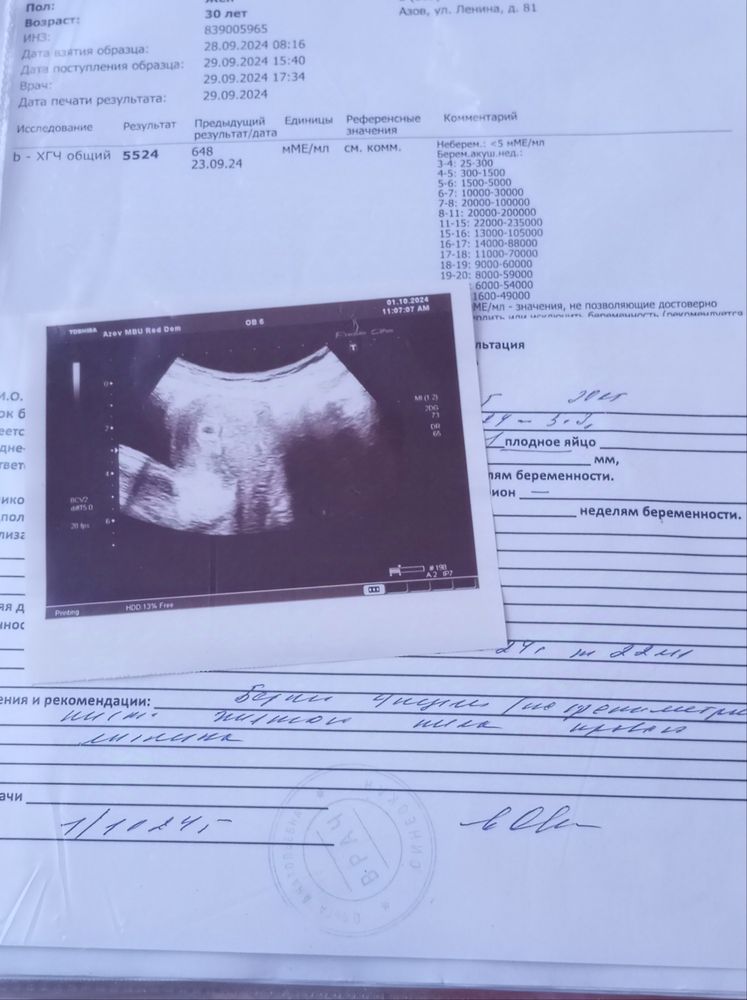

Лиза , ну смотри у меня хгч был вот такой в графе уже пишут акушерские недели, мне по УЗИ поставили уже 1 октября срок 4 недели. Все четко,по графе акушерские, по узи эмбриональные. Она сказала мне ПЯ соответствует сроку от зачатия Изображение

Марина, вот тут в графе указан по хгч уже акушерский срок как раз перед УЗИ, соответственно по хгч у меня акушерский, по УЗИ она сказала что соответствует размеру от зачатия и все хорошо, но это касаемо только ПЯ, вот в понедельник пойду на УЗИ и поствят мне срок 6 недель и уже размеры эмбриона и мешочка. Я потом сюда вам отвечу и покажу результаты Изображение

Лидия, вот у меня как раз 268 был 2 недели а 648 3-4 недели а 5524 УЗИ поставили 4 недели исходя из размера ПЯ